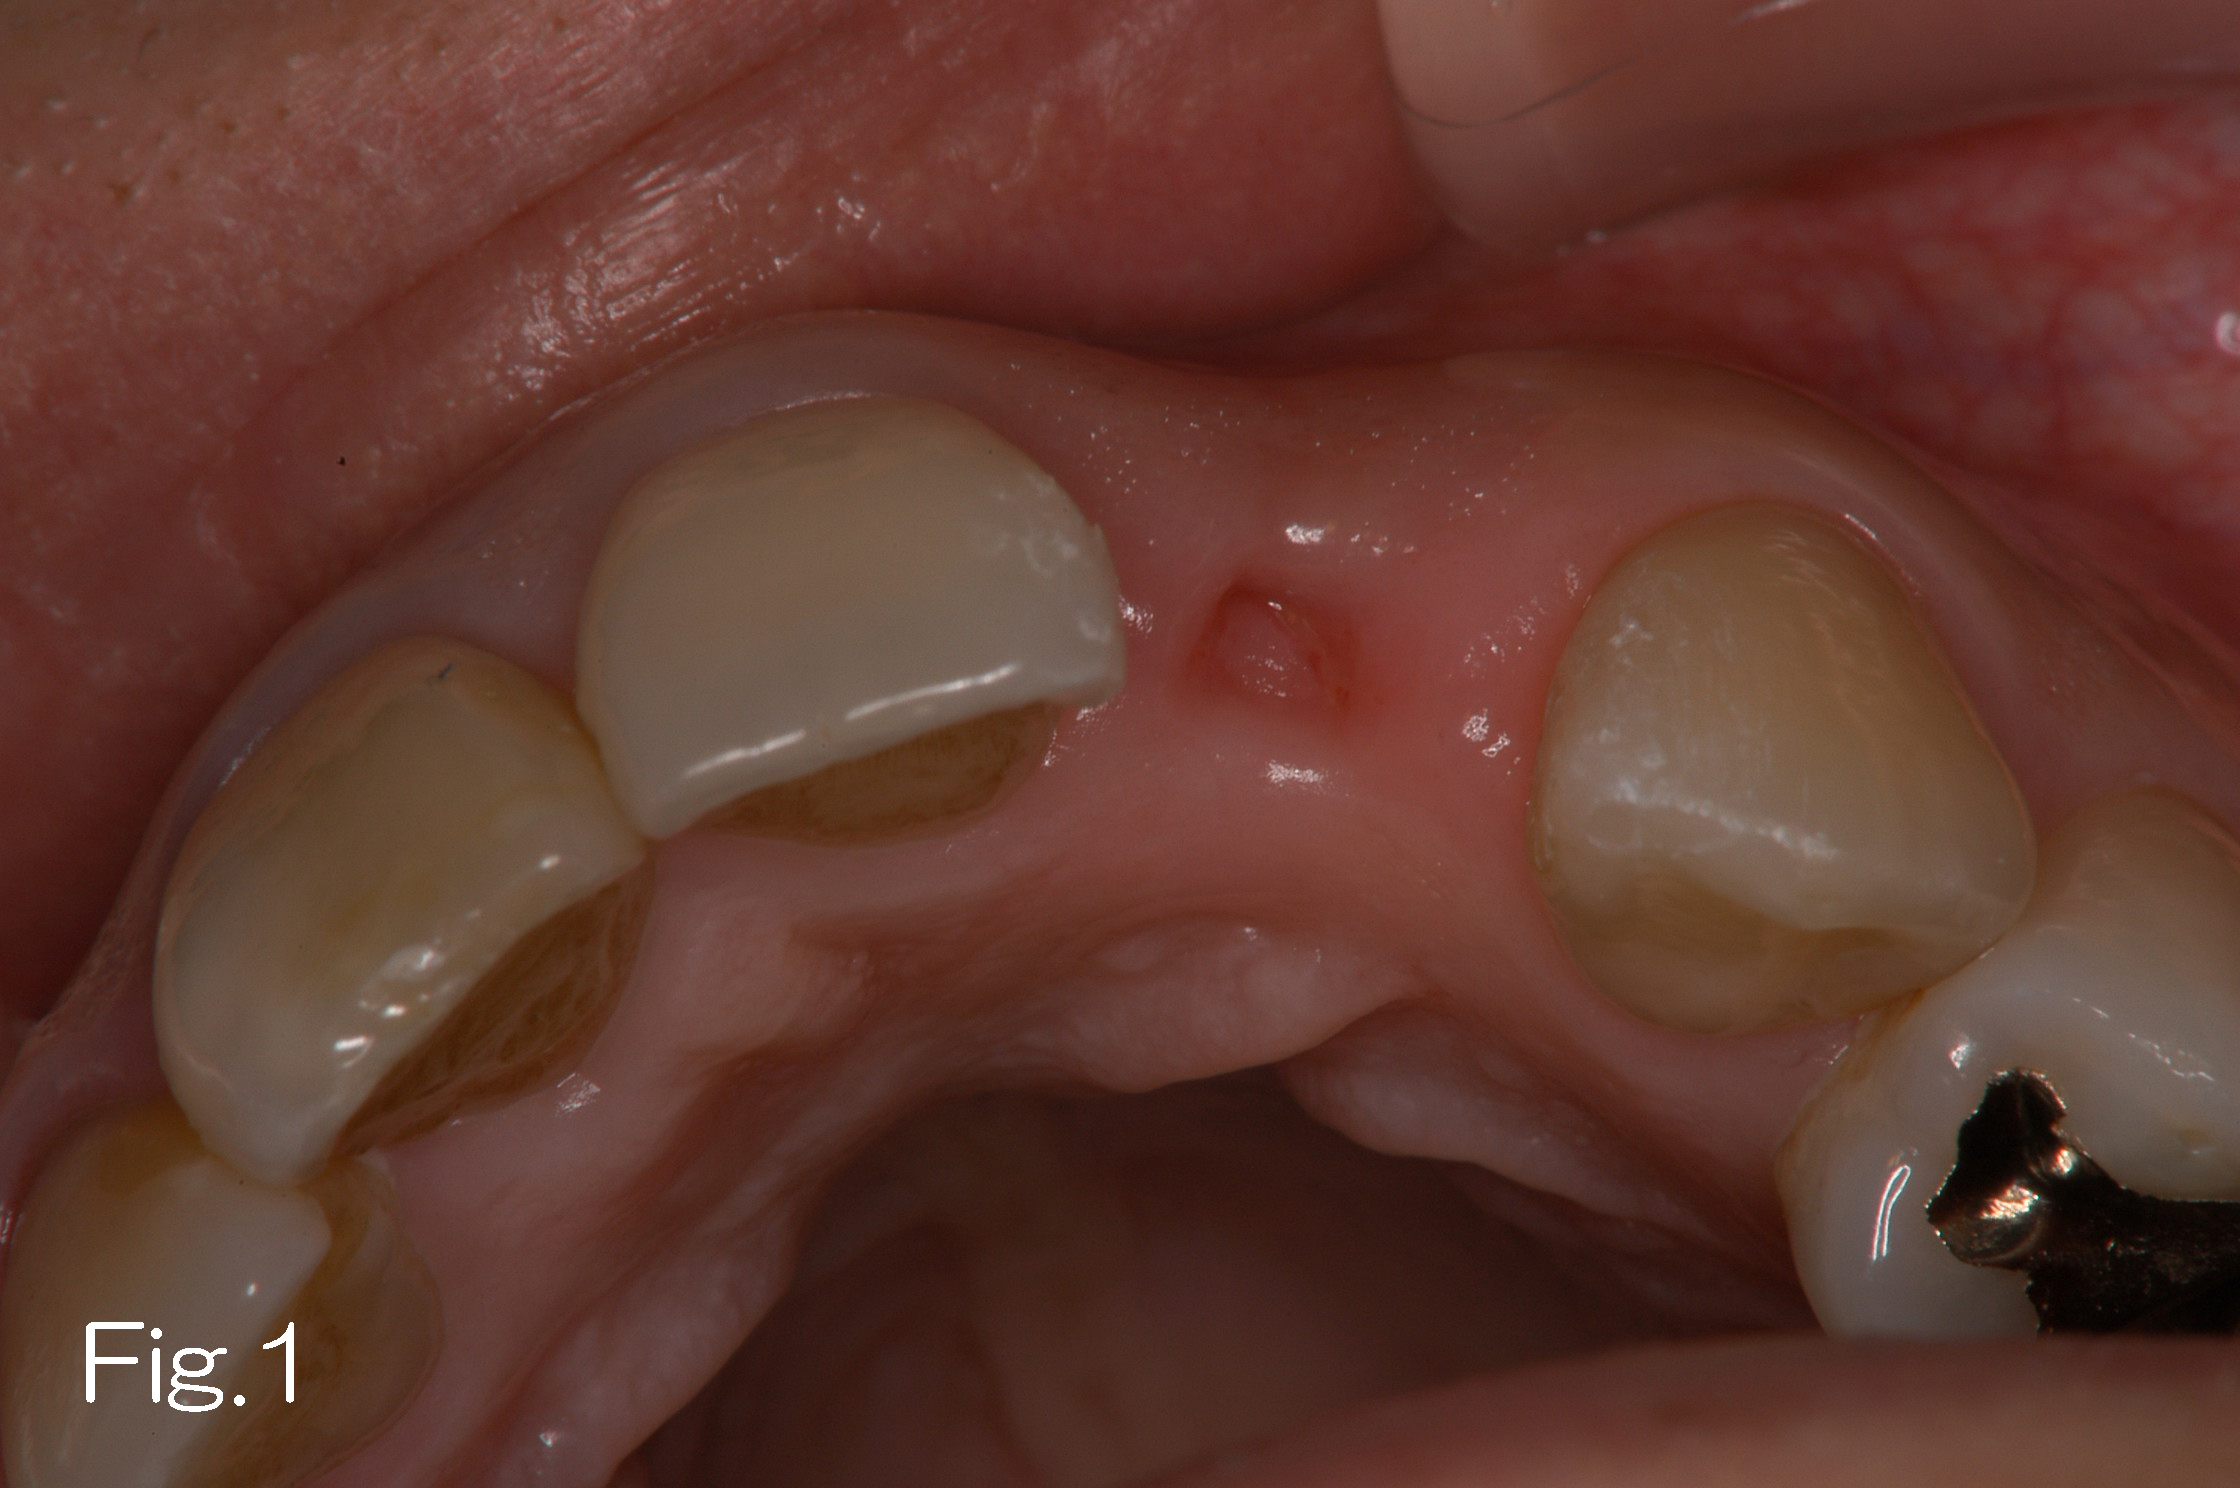

本症例は20代の女性で、抜歯後のインプラント治療を希望し紹介を受けた。

抜歯後の顎堤の吸収が大きく(Fig. 1)、インプラント埋入後約5mmの露出を認める(Fig. 2)。ドリリング時に採取される自家骨をインプラント露出部に移植しゴアテックス膜をかけGBRを行う(Fig. 3)。約6ヵ月の待機期間を経て2次手術と膜除去手術を行ったところ、十分な骨増生を認めた(Fig. 4)。十分な骨幅が確認でき(Fig. 5)、機能的かつ審美的な上部構造体を装着することが出来た(Fig. 6)。